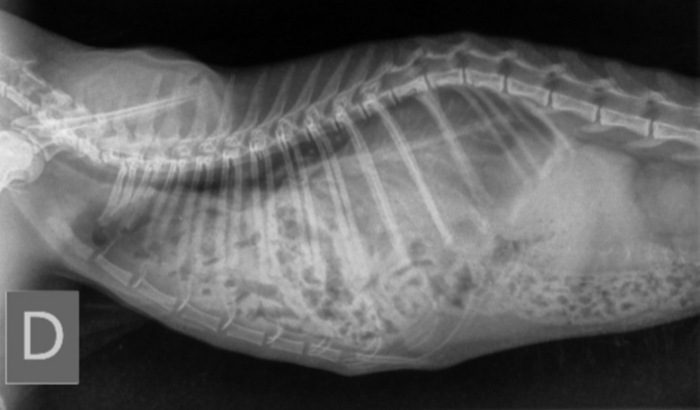

Ela ficou uns dias viajando comigo no caminhão até eu chegar em casa e levar ela no veterinário, depois da consulta e fazer um raio X descobrimos que ela tem Hérnia Diafragmática. Se ela não fizer a cirurgia ela tem de 6 a 12 meses de vida, se fizer tem pouca chance de sobreviver, mas de qualquer forma se deixar ela vai piorando até falecer.